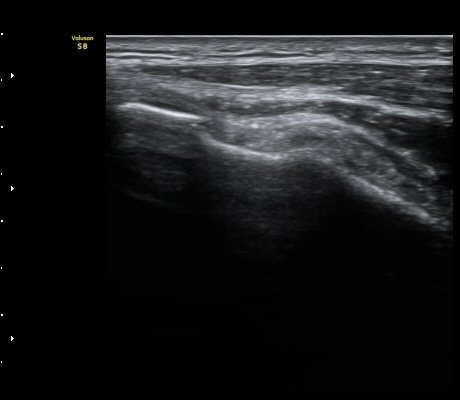

À̵ιڱ٠ÈûÁÙ Á¾´Ü¸é°Ë»ç¿¡¼­ ÈûÁÙÀÌ Àú¿¡ÄÚ°í °üÂûµÇ°í ÈûÁÙ ÁÖº¯ÀÇ ¼ö¾×Àú·ù°¡

¾Ö¸ÅÇÏ°Ô °üÂûµÈ´Ù(±×¸² 7). ŽÃËÀÚ ±ÙÀ§ºÎ¸¦ ÇǺÎÂÊÀ¸·Î ´©¸£´Ï ÈûÁÙÀÌ °í¿¡ÄÚ·Î

°üÂûµÇ°í ¼ö¾×Àú·ùµµ ¶Ñ·ÈÇÏ´Ù(±×¸² 8).